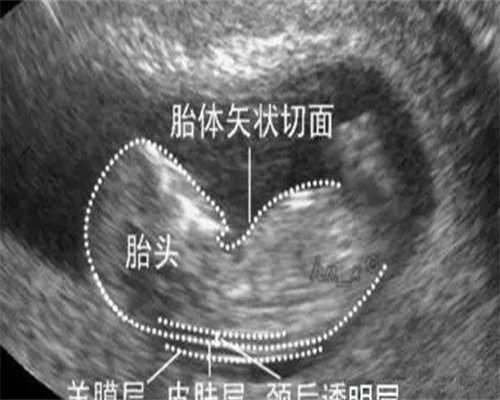

美国GE高清四维彩超